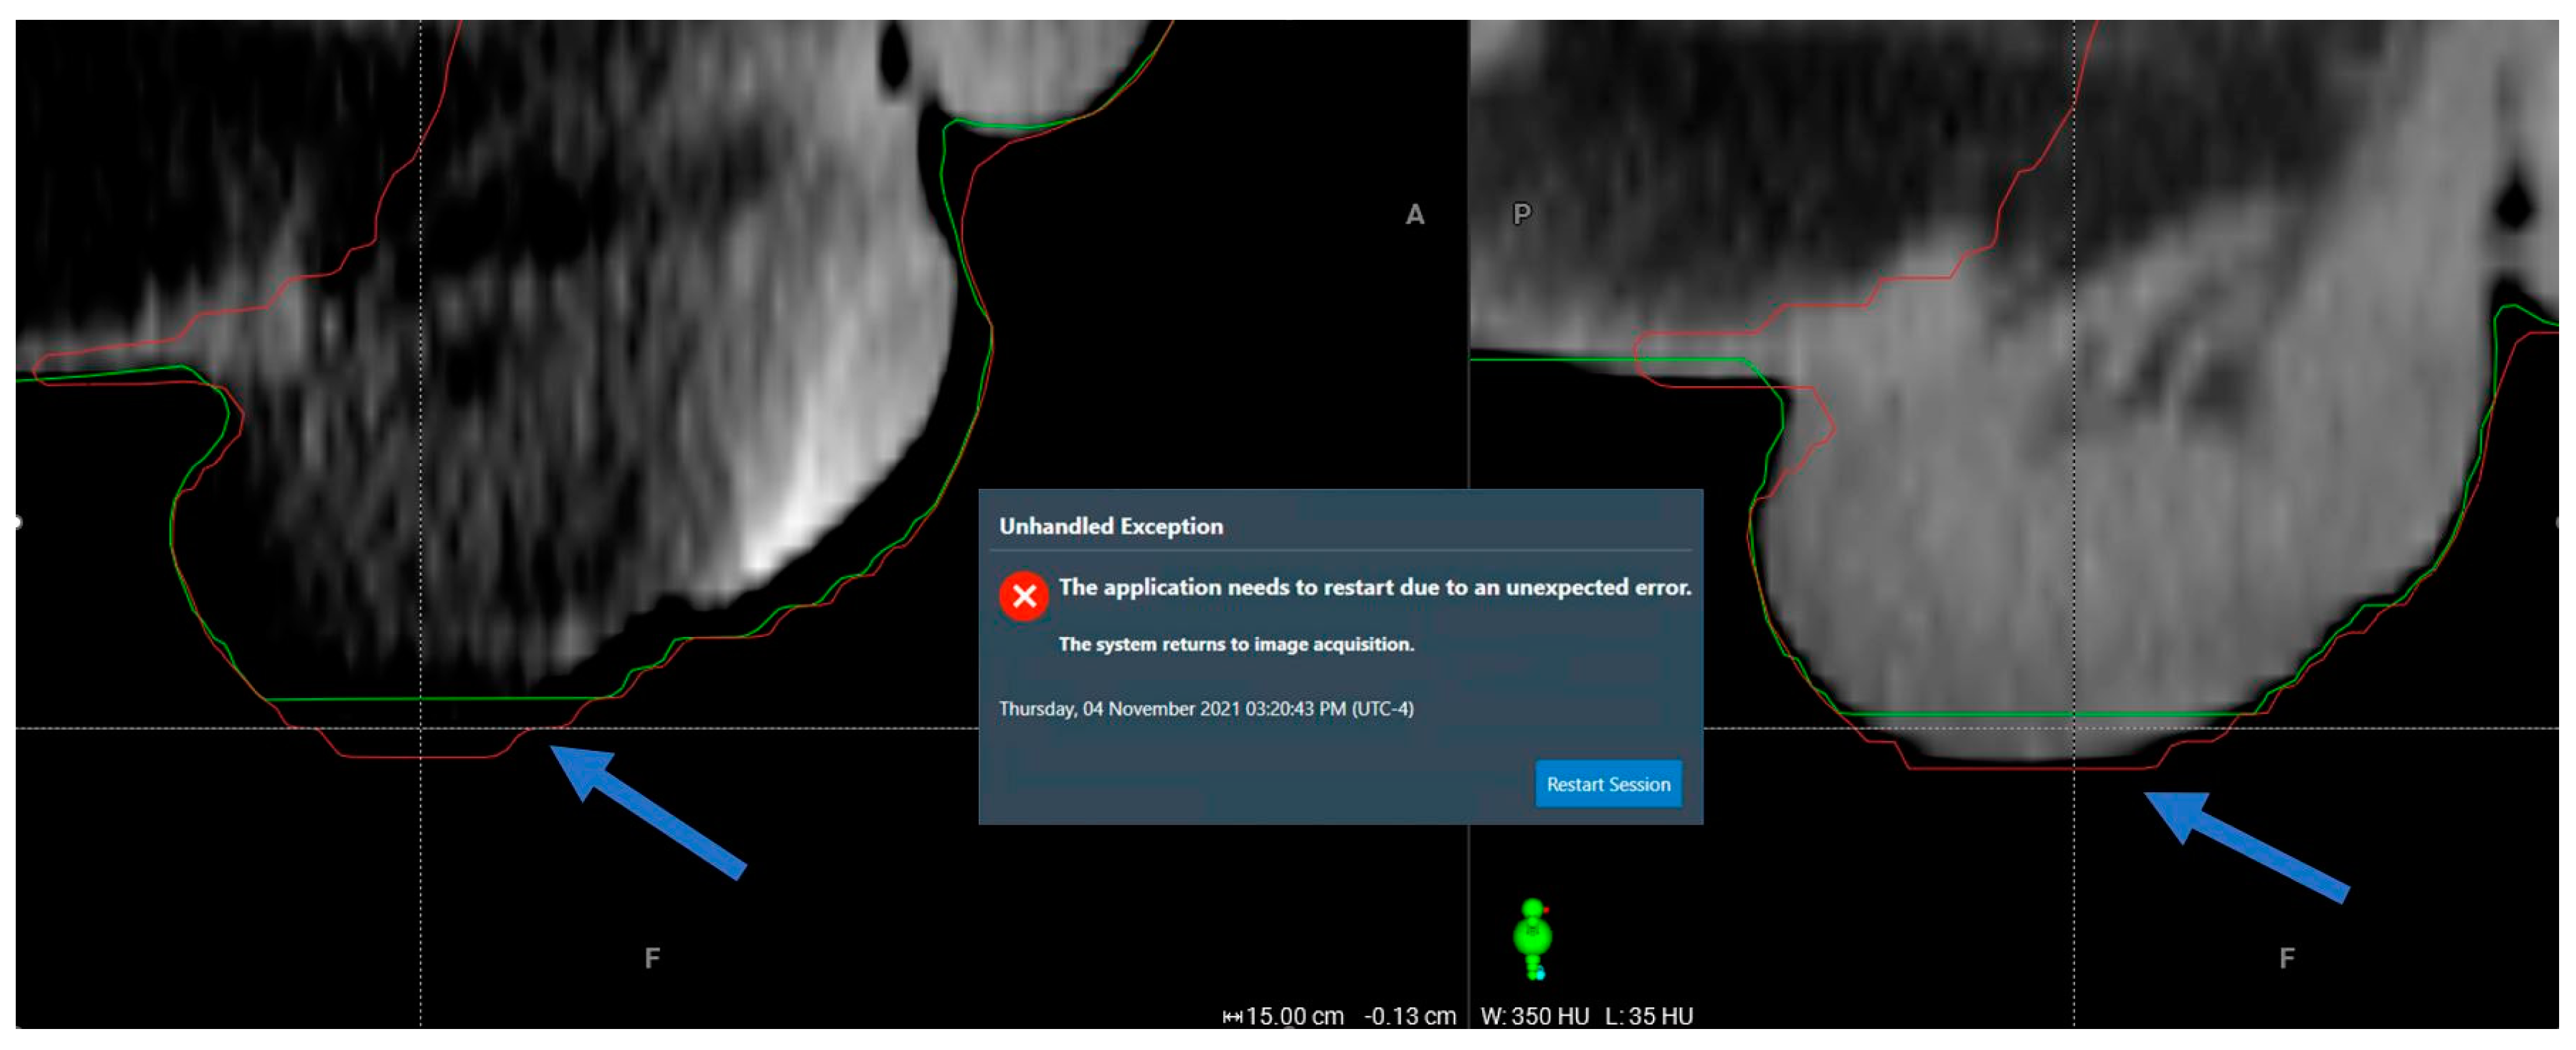

3.1. Aborted Sessions

| Adaptive plan unavailability due to internal software communication issues | 0.1% (1 instance) | N/A |